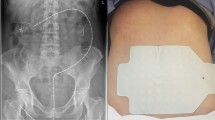

The resting colonic motor activity before and consecutively after spinal cord transection was recorded in male Sprague-Dawley rats. Recording probes were anchored surgically in the ascending and descending colon. Pressure changes were recorded on a dynograph using a low compliance perfusion system. A motility index took into account the amplitude, duration and frequency of contractions. Following a baseline recording animals were subjected either to spinal cord transection at T4 level or a sham operation. The recording sessions continued regularly on alternate days for the observation period of 3 weeks. Transection of the thoracic spinal cord markedly reduced the motility index of the distal colon on the first postoperative day. However, the motor activity gradually returned to pre-operative values after 7 days. Sham surgery did not influence the motor activity. These findings suggest that colonic motor activity is influenced by spinal shock and probably by different neural mechanisms mediating proximal and distal activities of the colon in rats.

Meshkinpour, H., Harmon, D., Thompson, R. et al. Effects of thoracic spinal cord transection on colonic motor activity in rats. Spinal Cord 23, 272–276 (1985). https://doi.org/10.1038/sc.1985.44